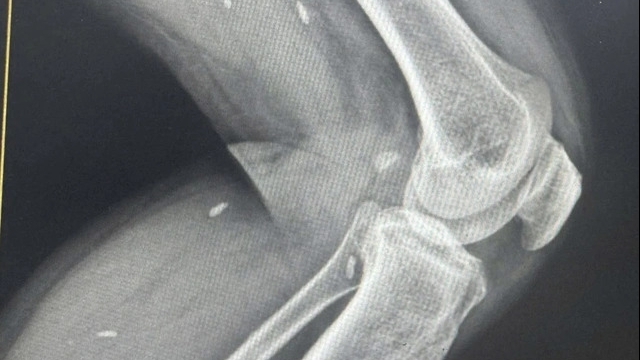

Bệnh nhi được chuyển đến BV Nhi TƯ vào chiều tối cùng ngày, bé vẫn còn lơ mơ, suy hô hấp, chẩn đoán sốc nhiệt do có thay đổi ý thức, rối loạn các cơ quan, rối loạn đông máu, có biểu hiện suy thận, tiêu cơ vân. Tuy nhiên sau khi được điều trị tích cực, thở oxy, cấp cứu tuần hoàn, cháu bé đã dần hồi tỉnh và hồi phục.